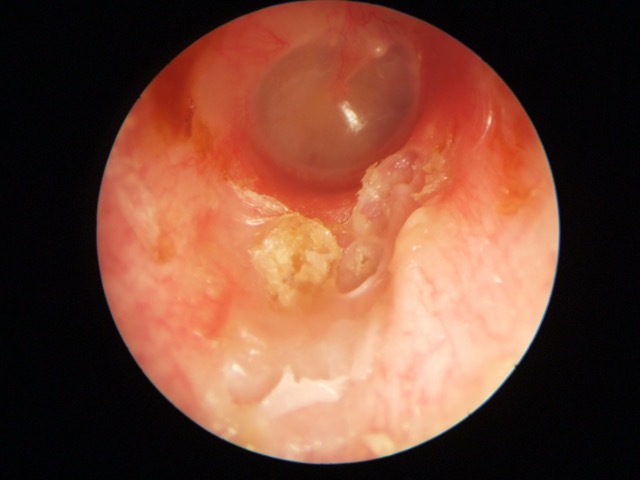

Cholesteatoma Clinical

Ear Canal